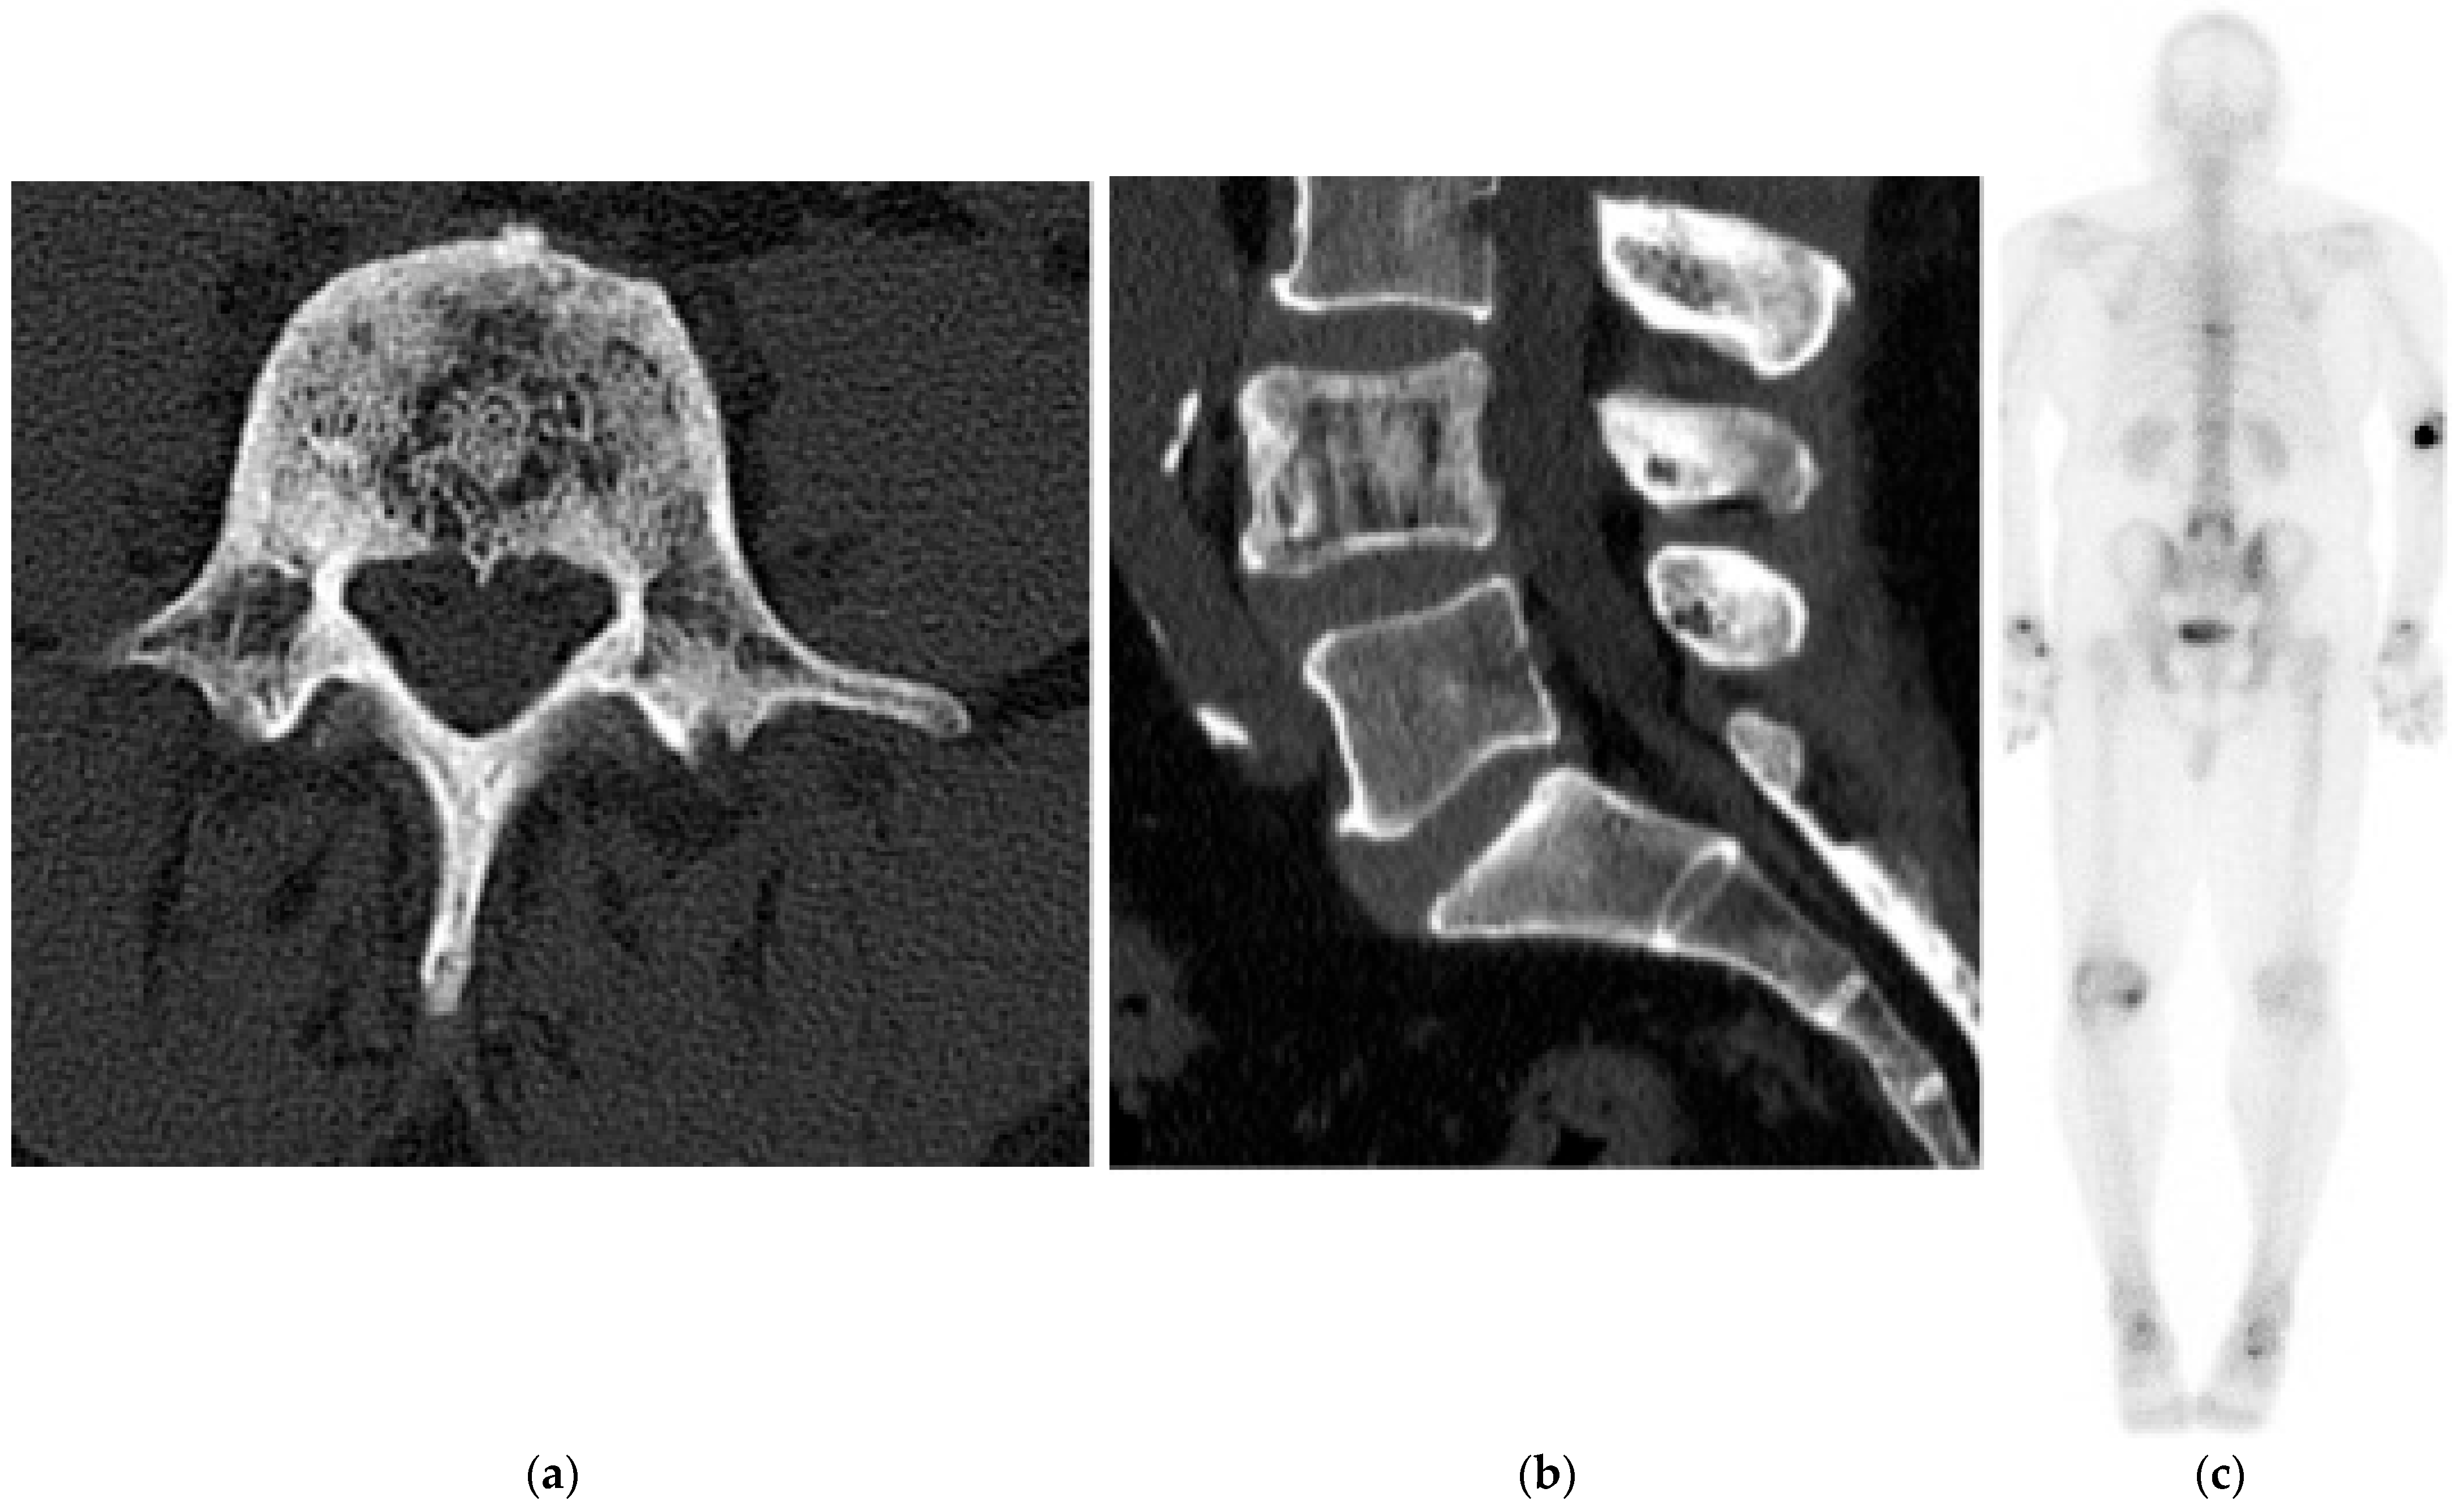

Paget’s Disease